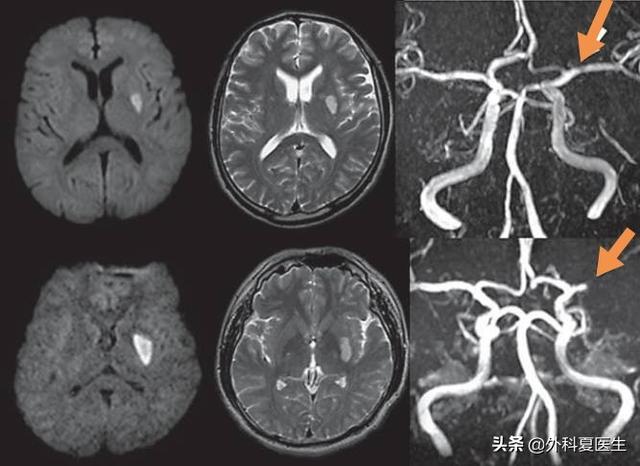

Tout d'abord, les vaisseaux sanguins cérébraux qu'il obstrue sont relativement petits, et la zone infarcie est également relativement petite.Il se produit généralement dans des vaisseaux de 100 microns et la zone d'infarctus, c'est-à-dire la taille de la lésion, est habituellement inférieure à 1 cm.

Deuxièmement, le site d'un infarctus cérébral lacunaire est mieux défini, alors que la localisation générale d'un infarctus cérébral est indéterminée.Les infarctus caverneux se produisent principalement dans les artères perforantes à l'intérieur du cerveau, telles que les artères moyennes, postérieures et basilaires les plus courantes. Par conséquent, les infarctus caverneux sont généralement localisés dans la région des ganglions de la base du cerveau, le thalamus, le pontin, etc.